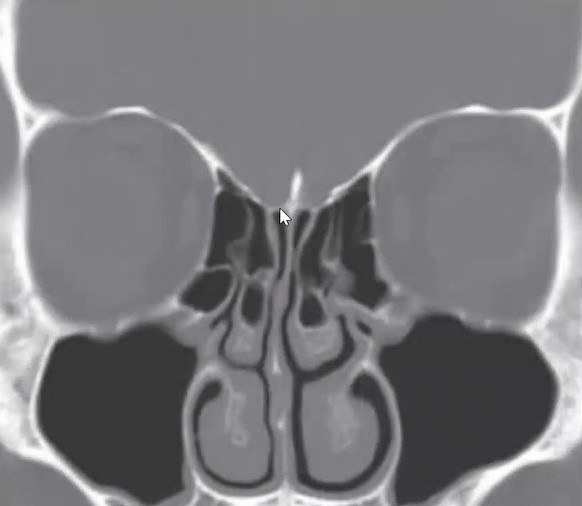

16

Qual a classificação de Keros da imagem?

A

Keros tipo 1 (1-3mm)

17

Q

Qual a classificação de Keros nessa imagem?

Keros tipo 3 (8-16mm)